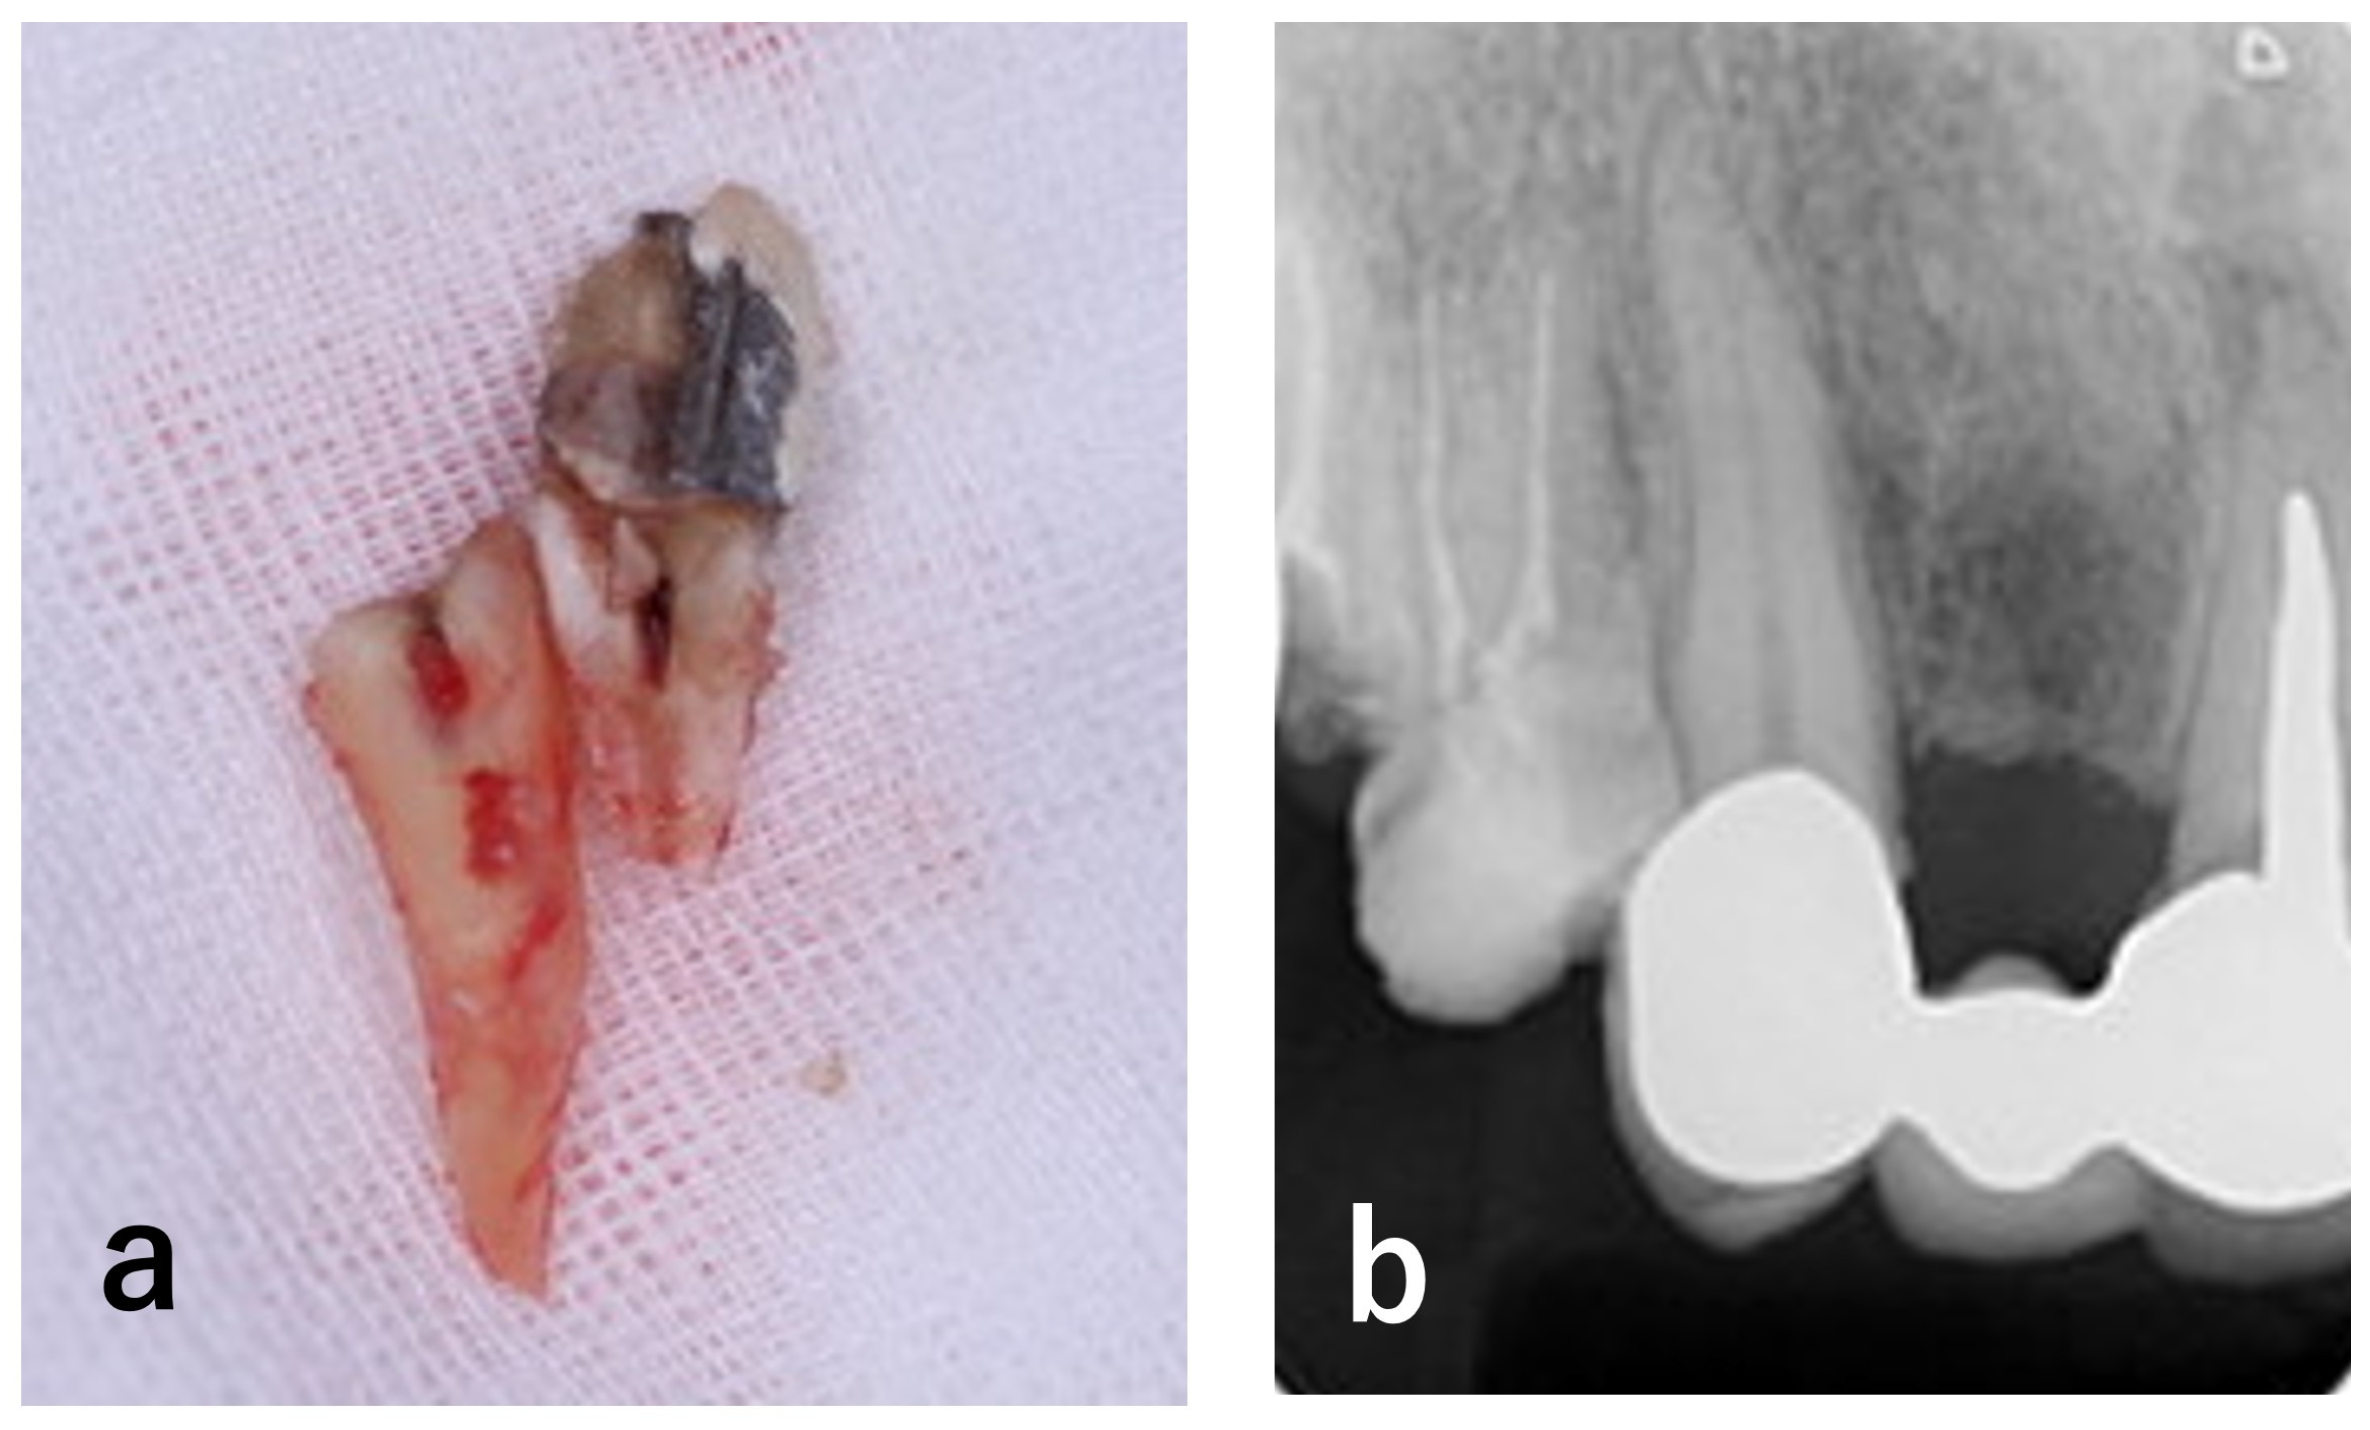

| 2 | Shortly after initial visit | Extraction of #13 | Vertical root fracture confirmed; extraction indicated (Figure 3) |